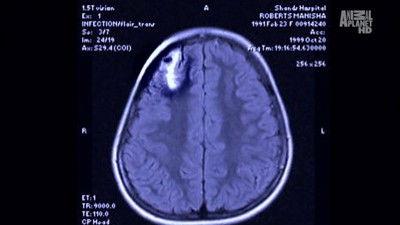

A seven-year-old girl suffers from seizures from a pork tapeworm after being adopted at the age of three from Nepal. A forty-five-year-old machinist deals with blurry and double vision, leaving him legally blind in his left eye, from a raccoon roundworm that he picked up from his turkey hunting. A forty-one-year-old anaethesiologists, along with twenty-eight other anaethesiologists from two different counties, suffer from stomach cramps and crippling diarrhea from the Cyclospora parasite after eating raspberries infected with human feces.